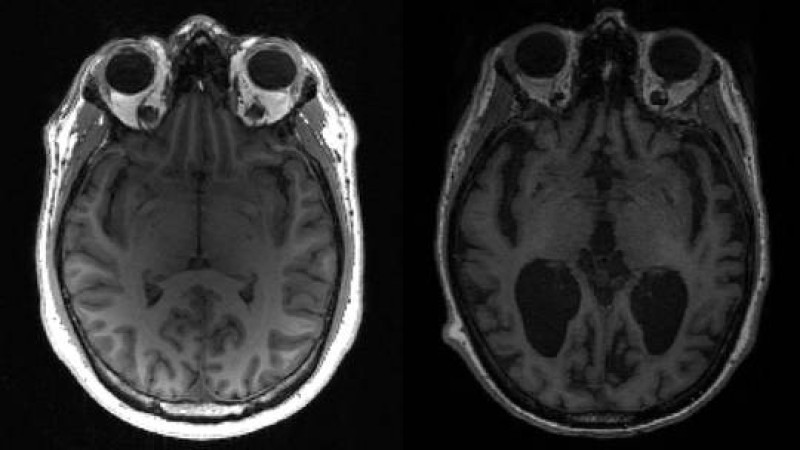

Um dos elementos mais perturbadores da condição é o pouco que se sabe sobre a transmissão. Em pelo menos nove casos, cuidadores e outros em estreito contato com indivíduos doentes desenvolveram sintomas semelhantes aos da parte enferma, sugerindo que a doença não só se espalha prontamente entre indivíduos sem parentesco, mas que pode haver fatores ambientais envolvidos. Alguns compararam a doença com a doença de Creutzfeldt-Jakob, uma doença cerebral fatal causada por proteínas deformadas chamadas prions, embora o exame feito não tenha comprovado casos da doença de Creutzfeldt-Jakob.